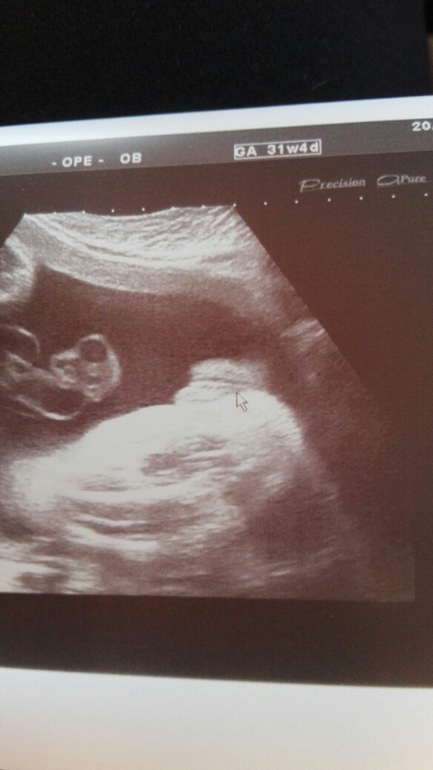

Дома. Мы поставили 2хярусную кровать. Так как места под отдельную кровать нет совсем. Катя поедет спать наверх, а маленькая будет спать внизу. Если переедем в большую квартиру, то подумаем над кроватью по-другому. А вот к роддому собираться я никак не начну. Да и вещи б малышке перестирать. Но вообще нет у меня синдрома гнездования. Не хочу я ничего. Так и дотяну, наверно, до последнего. Под кат добавлю фото с узи.

это личико(именно в этот момент мы увидели, как она показала нам язычок)))